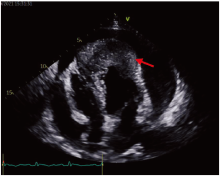

2021-10-09 13∶ 00行超声心动图, 见左右室壁心尖处可见不规则中等偏低回声浸润, 范围约6.5 cm× 3.1 cm, 与原心肌组织分界不清。左右室心尖部异常回声(占位可能); 主动脉瓣轻度返流; 大量心包积液; 室间隔、前壁、侧壁基底段至心尖部应变绝对值降低, 见图3。2021-10-09 14∶ 52行胸部平扫及增强CT显示:左下肺病变伴周围渗出, 大小约6.7 cm× 4.3 cm, 增强不均匀明显强化, 周围局部支气管狭窄闭塞, 考虑肿瘤性病变伴阻塞性肺炎可能并左下肺亚段型不张; 心包积液, 心尖部模糊, 增强见斑片状软组织占位, 考虑转移可能, 见图4。

| 图3 患者超声心动图图像 注:红箭头所示为心尖部占位可能。Fig.3 Echocardiography of the patient Note: The red arrow indicated the possible neoplasm at the apex. |

患者老年男性, 有冠心病高危因素, 急诊入院后结合心电图改变及心肌酶谱表现, 符合急性心肌梗死临床诊断标准, 故第一诊断考虑急性心肌梗死, 行冠脉造影显示前降支和钝缘支轻度狭窄, 左主干、右冠未见明显狭窄, 即排除该诊断。随后经心脏超声发现心尖部异常回声, 考虑心脏肿瘤可能; 完善胸部平扫及增强CT检查, 诊断左下肺肿瘤性病变伴心脏转移可能, 结合肿瘤标志物检查及心包穿刺、纤支镜活检病理明确, 最终诊断为肺癌伴心脏转移。